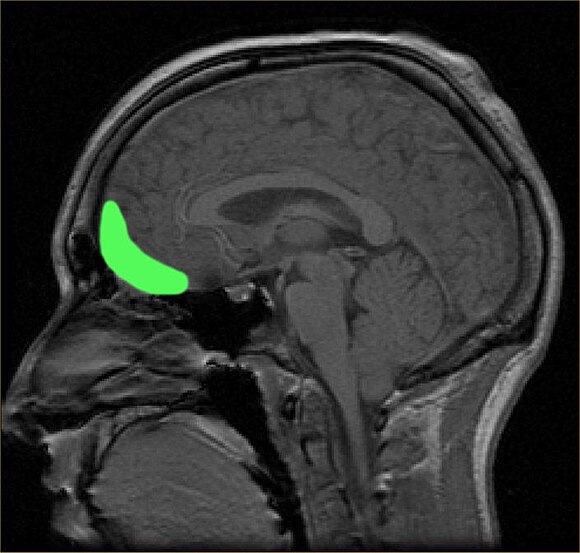

В исследовании приняли участие 352 взрослых футболиста-любителя. Ученые установили, что у тех, кто выполнял более 1000 ударов головой в год, наблюдались изменения в корковом интерфейсе серого и белого вещества (GWI) в орбитофронтальной области мозга, расположенной непосредственно за глазами.

Команда нейробиолога Майкла Липтона разработала новую методику визуализации, позволяющую детально исследовать внешние морщины мозга с помощью диффузионной МРТ. Эта техника выявила, что граница между серым и белым веществом становится более размытой у футболистов с большим количеством ударов головой.

Аспирантка Джоан Сонг, разработавшая метод анализа МРТ-изображений, отмечает, что у здоровых людей переход между тканями серого и белого вещества обычно резкий, тогда как у футболистов с большим количеством ударов головой этот переход становится менее четким.